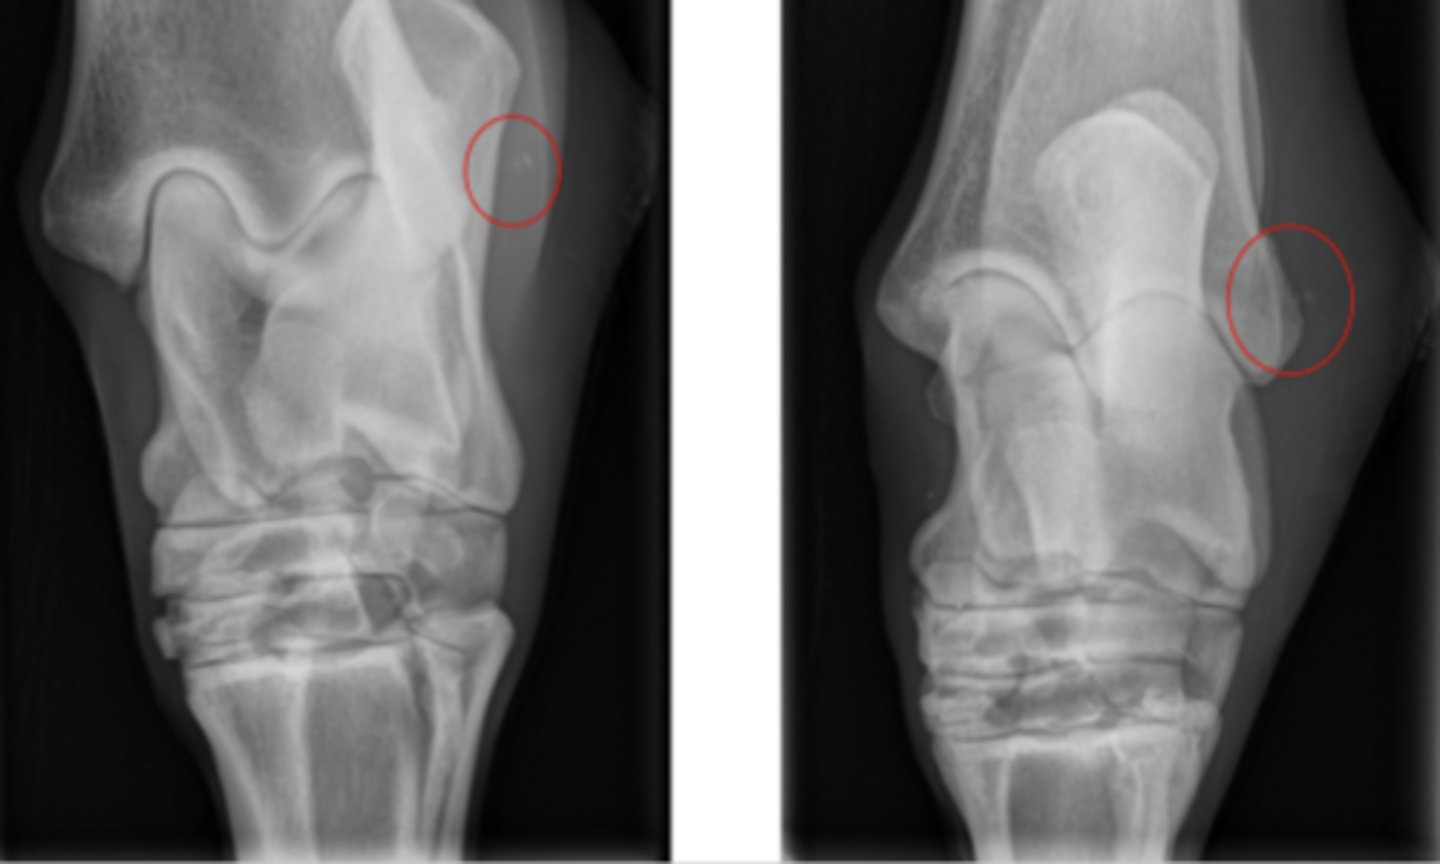

describe this wound

granulation tissue

epithelial tissue

sloughing

lots of movement

not good blood supply

not granulating over foreign body

infected

what is this main reason for the chronic non-healing wound

Periosteal elevation

Soft tissue swelling

bone fragment - acting as a foreign body

debride thoroughly

flush